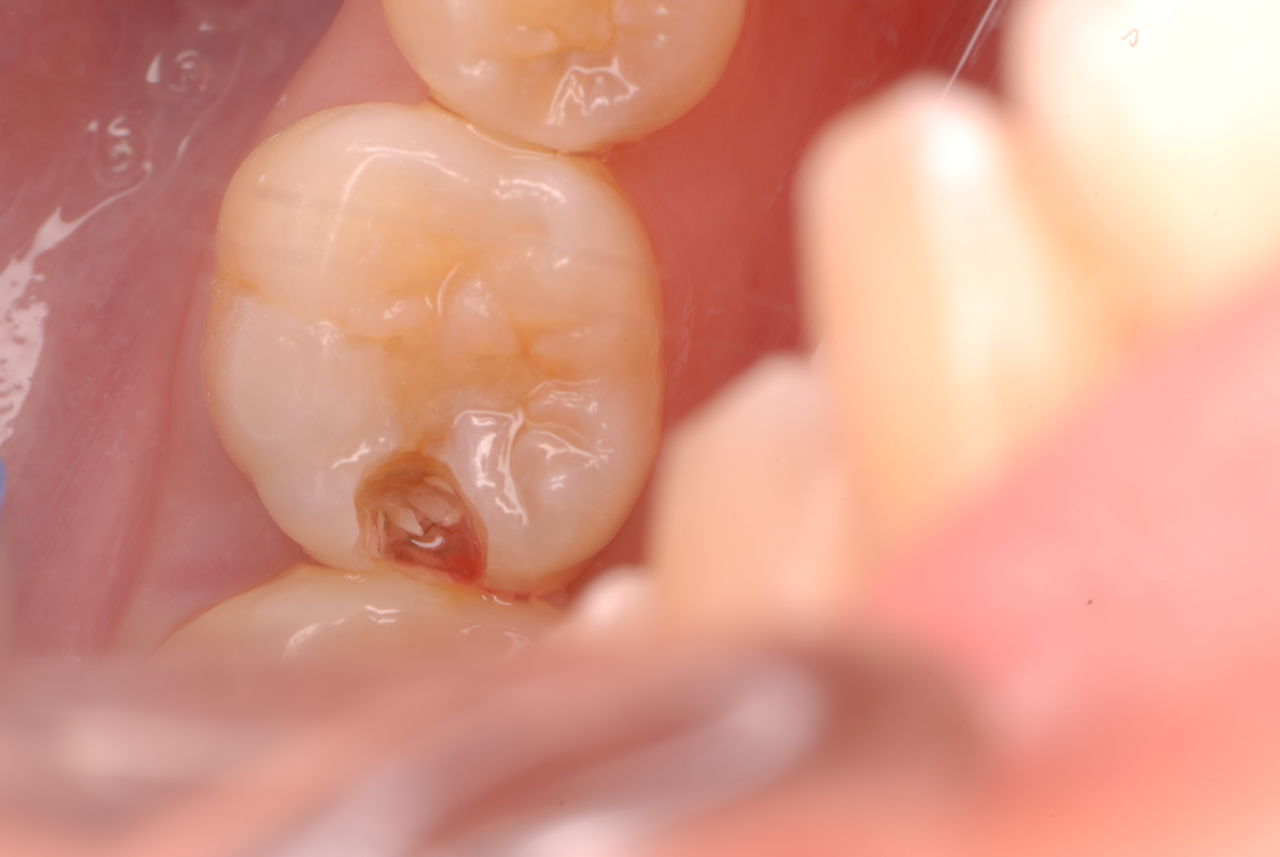

写真左下の親知らずが痛くなり抜歯しました。その後歯茎を除去して虫歯を露出させる処置を二回ほどしています。

レントゲンでは小さいですが、こう言う虫歯が一番怖いのです。

治療の成功率は極めて悪くすぐ再発しやすいのです。